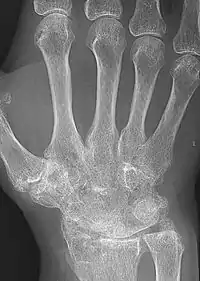

X-rays of the hands and feet are generally performed when many joints affected. In RA, there may be no changes in the early stages of the disease or the x-ray may show osteopenia near the joint, soft tissue swelling, and a smaller than normal joint space. As the disease advances, there may be bony erosions and subluxation. Other medical imaging techniques such as magnetic resonance imaging (MRI) and ultrasound are also used in RA.[20][63]